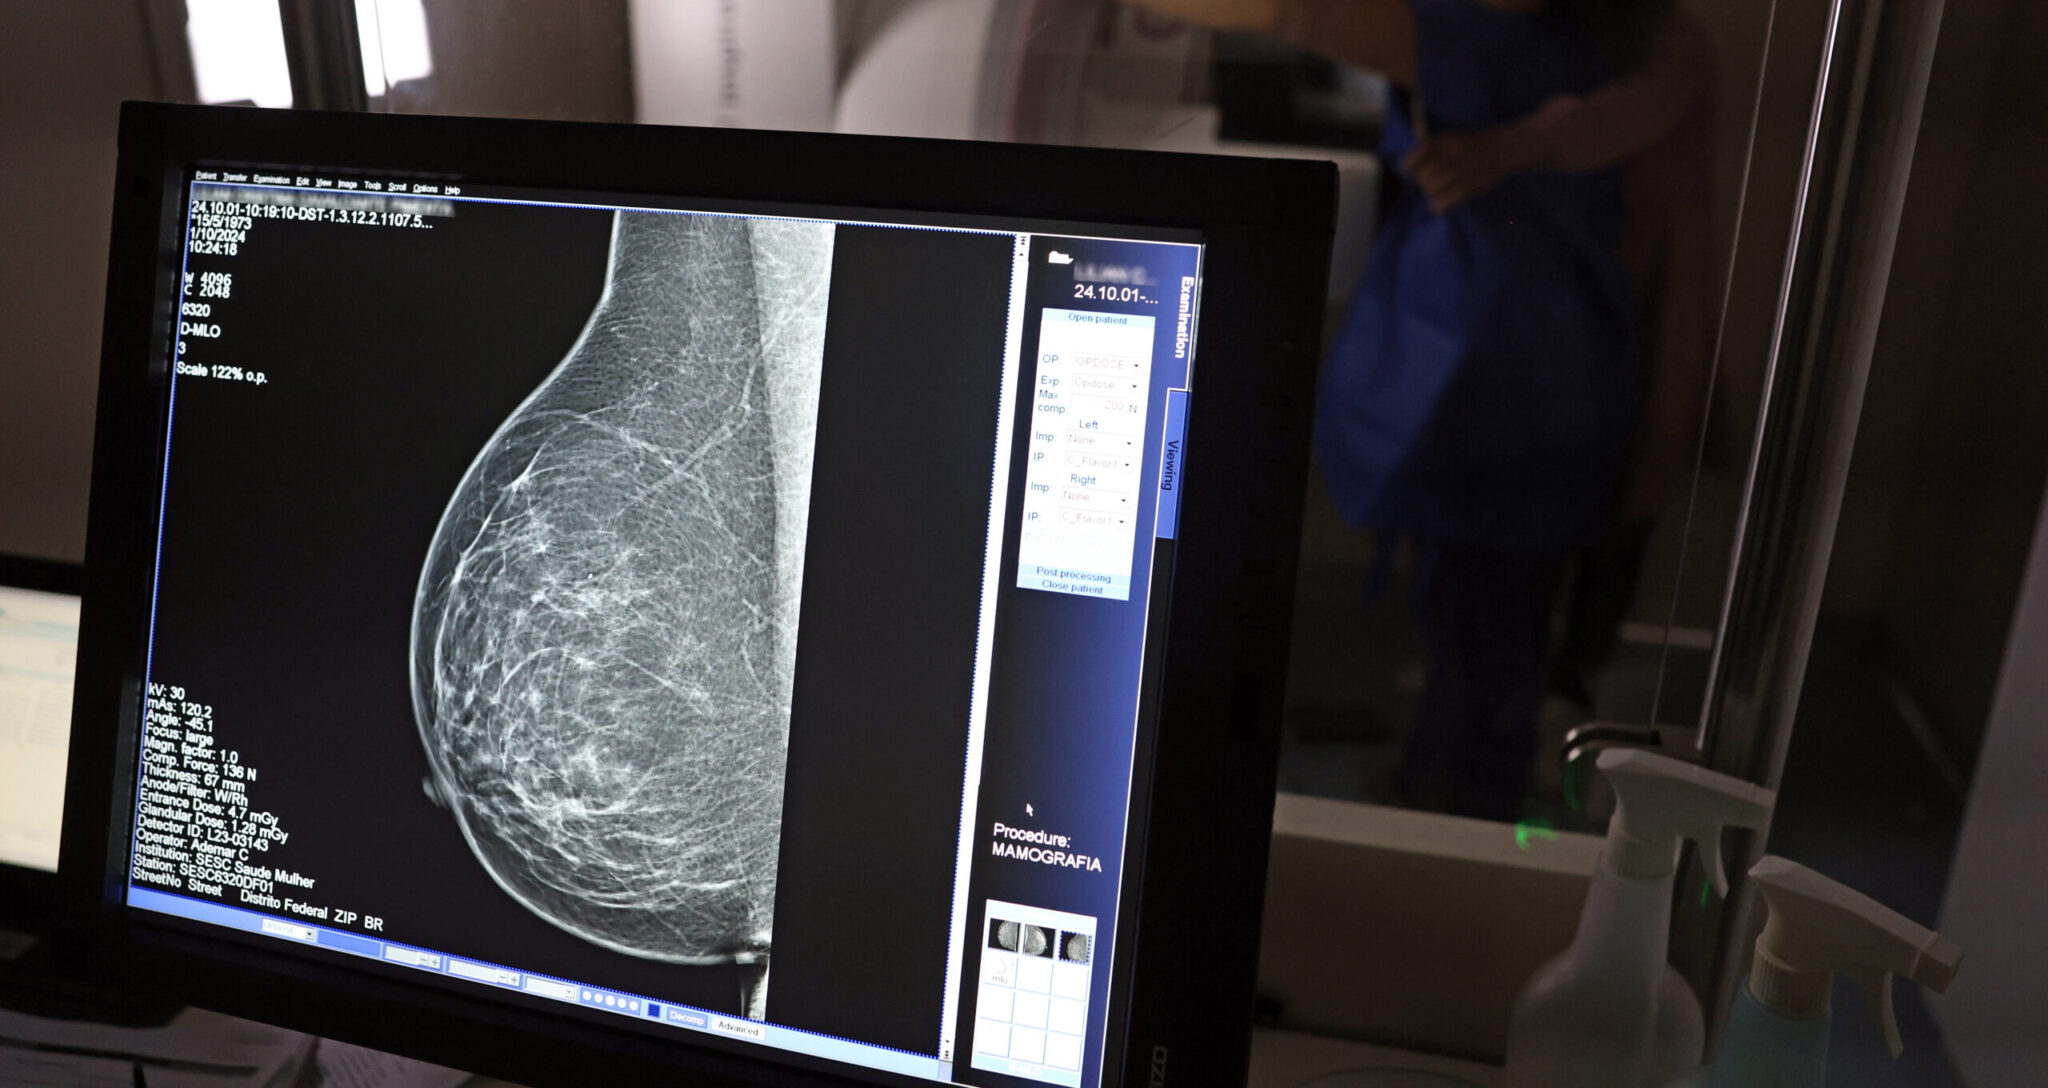

Com mais de 57 mil mamografias realizadas em 2025, o Piauí ampliou significativamente o acesso ao diagnóstico precoce do câncer de mama, especialmente entre mulheres a partir dos 40 anos. Como parte das ações de reforço ao tratamento, o estado recebeu, na quinta-feira (23), uma remessa com 224 unidades do medicamento Trastuzumabe Entansina, recém-incorporado ao Sistema Único de Saúde (SUS) para casos avançados da doença.

A rede estadual conta com 43 mamógrafos fixos e o serviço itinerante dos Caminhões da Mamografia, que percorrem os municípios levando o exame a quem mais precisa. O foco principal tem sido nas mulheres entre 40 e 49 anos, faixa etária que passou a ser atendida sob demanda, conforme nova orientação do Ministério da Saúde.

Foto: Ascom Sesapi“Outubro Rosa é um mês para toda sociedade se concentrar na proteção às nossas mulheres, sobretudo na prevenção do câncer de mama. Por isso estamos descentralizando, não apenas com mutirões, mas com salas permanentes de mamografia. É o caso da Central de Diagnóstico de Valença, que agora atende toda a região sem fila de espera. Viva as mulheres, viva o Outubro Rosa!”, declarou o governador durante visita ao hospital da cidade.

A técnica em radiologia Ana Vitória atua na Central de Diagnóstico de Valença e confirma o impacto direto na vida da população. “Antes o exame só era disponibilizado em clínica particular. Agora, mulheres de toda a região vêm aqui, fazem o agendamento e realizam o exame. Atendemos mulheres a partir dos 40 anos, sem fila, com estrutura pública. Isso melhorou muito a vida das pessoas”, afirma.